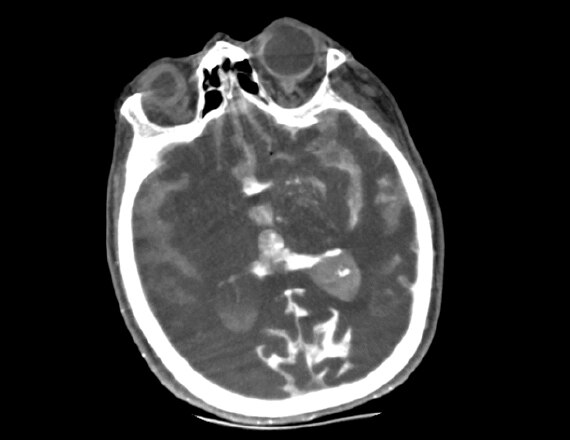

A patient with suspected TIA or stroke will typically receive a general and neurological examination followed by diagnostic brain imaging, performed immediately on arrival so that treatment can be started promptly.3 Optimal scanning coupled with workflow applications and protocols designed for stroke help deliver accurate and quick diagnosis to impact patient outcomes.

Revolution brand of CT systems

Capable of acquiring neuro perfusion and CTA of the brain in a single exam to enable comprehensive functional and anatomical assessment.

FastStroke CT Application

Simplifies and organizes CT images for fast evaluation of Stroke patients.

Fast Brain protocol with HyperWorks

Providing structural as well as vascular information with improved resolution and precise characterization in 5 minutes.